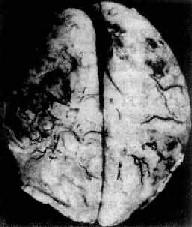

肉眼观,脑脊膜血管高度扩张充血,病变严重的区域,蛛网膜下腔充满灰黄色脓性渗出物,覆盖着脑沟脑回,以致结构模糊不清(图16-10),边缘病变较轻的区域,可见脓性渗出物沿血管分布。在渗出物较少的区域,软脑膜往往略带混浊。脓性渗出物可累及大脑凸面矢状窦附近或脑底部视神经交叉及邻近各池。由于炎性渗出物的阻塞,使脑脊液循环发生障碍,可引起不同程度的脑室扩张。

化脓性脑膜炎

图16-10 化脓性脑膜炎

蛛网膜下腔内有多量脓液堆积以致大部分脑表面的沟回结构不清;脑膜血管高度扩张充血